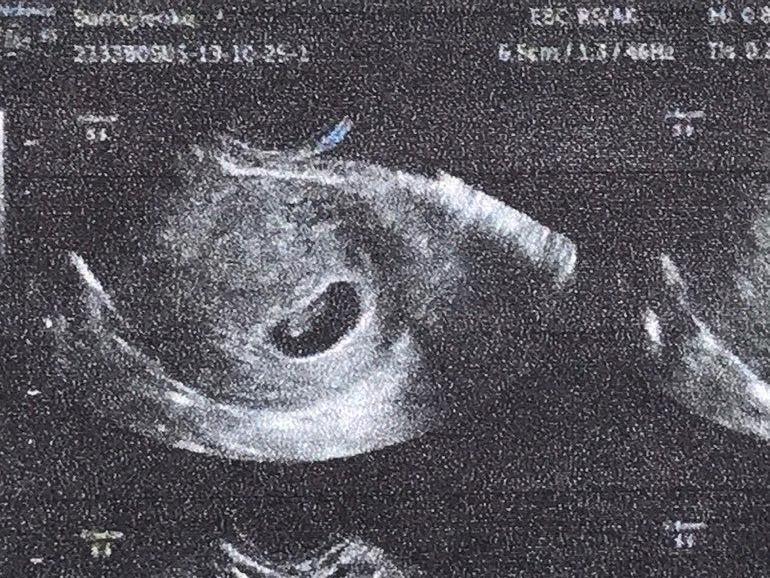

Побывала сегодня на УЗИ. Нашли мою креветочку (на фото видно плохо, но на экране точно креветочка!). Детка маленькая, но сердцебиение хорошее (на моменте замера сердцебиения я от счастья соплей наглоталась 😝).

Наши размерчики:

ПЯ 16 мм

КТР 4,4 мм

ЖМ 2,1 мм

ЧСС 124 уд/мин

Есть киста ЖТ - 46 мм. Прогестерона нагнала нормально 😅

Врач сказал все ок, поставил развивающуюся беременность, со сроками не париться - сказал все догоните, главное - отличное СБ. Следующий замер на скриннинге в 12 недель.